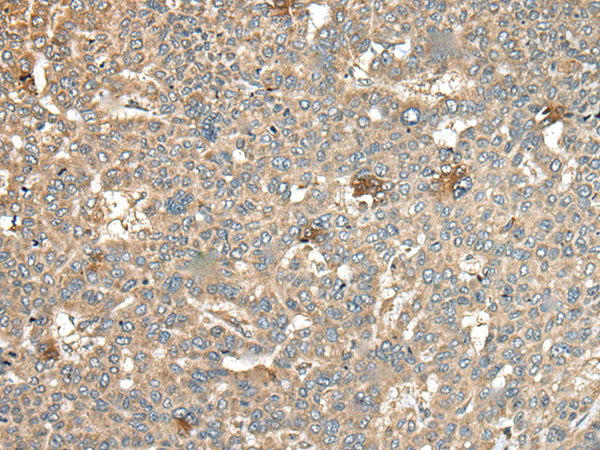

分类: 科研抗体货号: P09389别名:应用: WB,IHC反应种属: Human